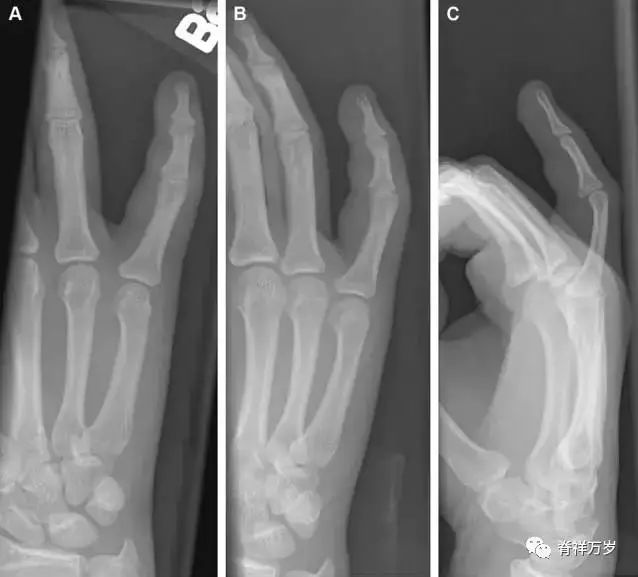

34.钩状骨骨折

钩状骨骨折可发生于体部和钩部,钩部骨折更多见,可合并有第 4、5 腕掌关节脱位。受伤机制由直接*力暴**或腕横韧带撕脱伤所致。骨折征象包括钩部无显示、骨皮质边缘模糊、硬化或双密度影等。常规的正侧位常无法明确诊断,需要加拍腕管位,可清晰显示其钩部。

图 5 打高尔夫球后腕部急性疼痛。常规腕关节 X 线片正常(X)。腕管位片(B)隐约可见钩部横行骨折(虚线箭头),CT 检查(C、D)进一步明确了诊断。

35.三角骨骨折

三角骨骨折是除舟状骨骨折外腕关节常见的骨折之一。其背侧是背侧桡腕韧带的附着点,因此背侧骨折更常见。常规正侧位片基本可明确诊断。背侧骨折可在侧位片上看到一小骨块。

图 6 三角骨骨折。(A)前后位片骨折不明显,(B)仅在侧位片上见一小骨块(短箭头),伴有软组织肿胀(长箭头)。